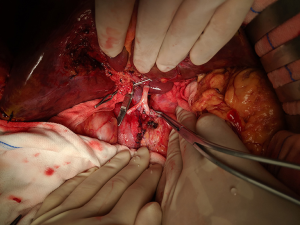

After routine en bloc acquisition of the donor liver, pancreas, and both kidneys, the abdominal aorta was cut between the renal artery and the SMA, the inferior vena cava was transected below the liver and above the right renal vein, the donor pancreas and liver were preserved, and the renal junction kidney group was trimmed. The surrounding tissues, including lymphatic vessels, the hepatic plexus, and surrounding connective tissue, were carefully dissected at the hepatic pedicle at the first porta hepatis. The common bile duct, hepatic portal vein, and PHA were freed from the right to the left, respectively. The distal part of the common bile duct was transected and doubly ligated with no. 7 and 4 silk sutures, the hepatic portal vein was transected approximately 1.5–2 cm away from the outlet of the pancreas, and the PHA was freed in the direction of the pancreas. The common hepatic artery and gastroduodenal arterial arch could be observed, the arterial variation was explored, then the integrity of the arterial arch was obtained. The PHA was transected approximately 0.5 cm away from the distal end of the arterial arch, the PHA transection was closed with a 5-0 atraumatic vascular suture, and the opening of the donor liver end was examined (Figure 1). If the hepatic artery was variant, the variant hepatic artery branches were divided separately (Figures 2 and 3). The SMA and its branches were obtained for liver reserve (Figure 4).

The donor liver was trimmed in vitro and revascularization was performed. After trimming the SMA and its branches and selecting the appropriate branches, the hepatic artery and SMA branches were end-to-end sutured with appropriate atraumatic vascular sutures, fixed at 4 points, then intermittently sutured. The reconstructed artery was then anastomosed end-to-end with the hepatic artery in vivo (Figures 5 and 6). If the PHA of the donor liver was not variable but short, end-to-end anastomosis was performed with the SMA and the PHA of the donor liver in vitro, and end-to-end anastomosis was performed between the SMA of the donor and the PHA of the recipient liver after the portal vein was opened (Figure 7).